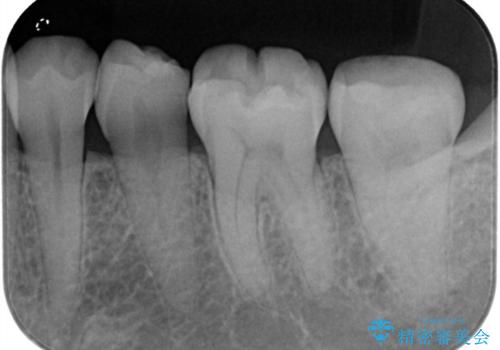

樋状根(といじょうこん)の根管治療